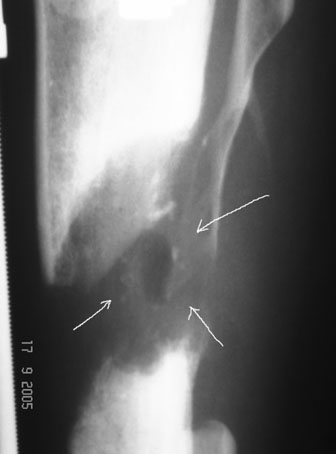

С места аварии в районную больницу, где произвели ампутацию правой голени. Дальше в клинику спец. помощи, где на левой голени были удалены нежизнеспосбные инфицированные отломки, (дефект 13 см) и наложен аппарат Гофмана. Детали неизвестны. Со слов больного, инфекционный процесс левой голени купирован не был. В феврале аппарат был снят и произведен остеосинтез гвоздем (before1;2). В мае, объективно: В нижней трети голени функционирует свищ, отделяемое гнойное: золотистый стафилокок, чувствительный к большинству антибиотиков.

Рентгенологически определяется дистракционный регенерат удовлетворительной плотности и наличие в нем полости (now 1;2;3).